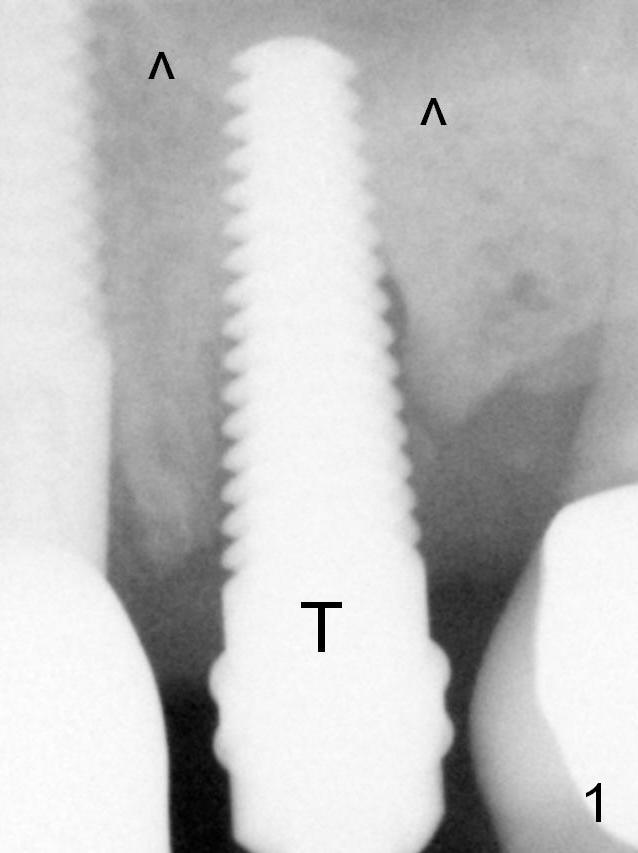

Extraction of the affected 2nd premolar is easy; the apical bone is so hard that drill (2 mm) and reamers (2.5 and 3 mm) have to be used for osteotomy, followed by insertion of a 4.5 mm tap with stability (Fig.1 T). The sinus floor (^) is lifted. There is no sinus membrane perforation. There is no sign of sinus membrane perforation before placement of a 4.5x14 mm implant (Fig.2 I); sinus lift is performed (*, with mixture of autogenous bone (from reamers), allograft and Osteogen). Arrowheads: remaining mesial and distal sockets, which will be bone grafted after provisional fabrication. Bone density in the mesial and distal sockets increases after bone graft (Fig.4: arrowheads). The distal threads appear not covered by the bone, with mild distal crestal bone resorption, 2.5 months postop (Fig.11 >). Panoramic X-ray is taken 3 years and 1 year 5 months post cementation for #12 and 13, respectively (Fig.12). The bone height increases at #13. Intraop Modification of Immediate Provisional Last Next Xin Wei, DDS, PhD, MS 1st edition 07/30/2015, last revision 05/25/2018 |